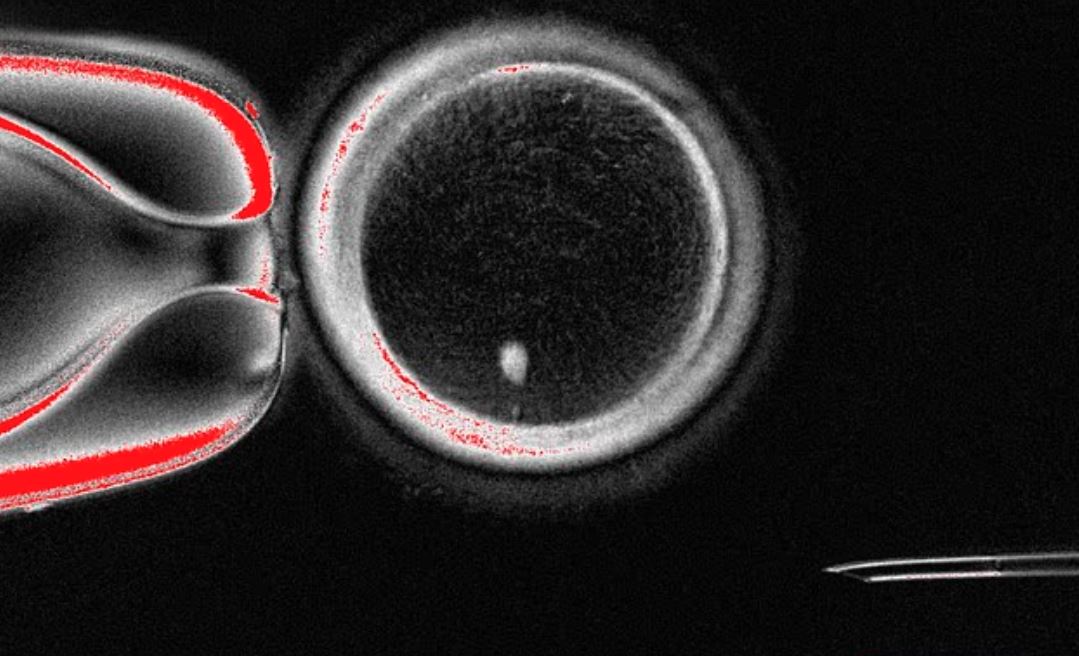

실제 실험에서, 이렇게 만들어진 82개의 인공 난자를 수정시킨 결과, 약 9%가 초기 배아 단계인 '배반포'까지 성공적으로 발달했다고 합니다.

▪ 낮은 성공률 : 실험에서 91%의 인공 난자는 수정 이후 제대로 발달하지 못했습니다.

▪ 안전성 문제 : 성공적으로 발달한 소수의 배아에서도 '염색체 이상'이 발견되었습니다.